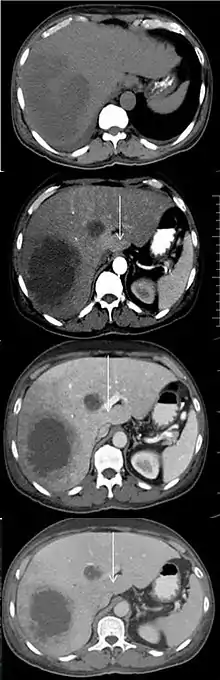

An abscess and a THAD (white arrow) on a contrast CT in native, arterial, portal and delayed phase.[1]

Transient hepatic attenuation differences (THAD) are areas of enhancement during the arterial phase of contrast CT of the liver. THAD is thought to be a physiological phenomenon resulting from regional variation in the blood supply by the portal vein and/or the hepatic artery. THAD may in some cases be associated with liver tumors such as a hepatocellular carcinoma.[2]